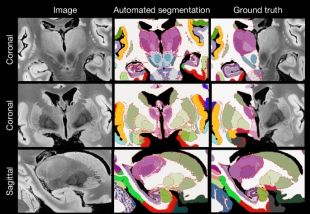

Un estudi liderat per un investigador de la UdG crea el mapa més complet del cervell humà

Un equip internacional d’investigadors ha desenvolupat el mapa més complet i detallat del cervell humà fet fins ara, gràcies a l’aplicació de tècniques avançades ...